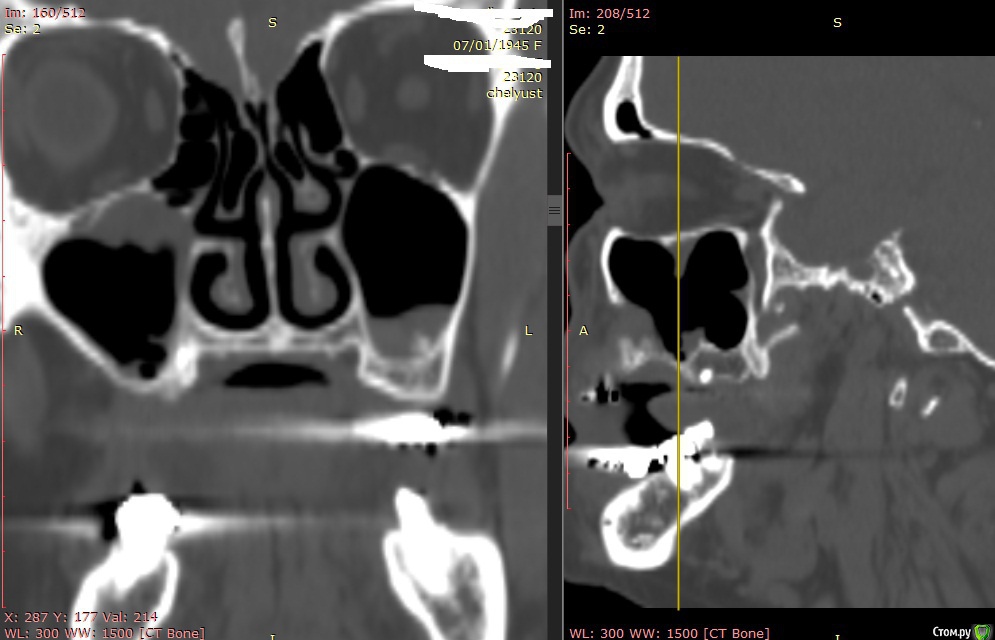

Alexey Doc Опубликовано 29 апреля, 2015 Поделиться Опубликовано 29 апреля, 2015 В клинику с целью протезирования обратилась пациентка 70 лет.Ортопед направил на консультацию. В анамнезе: со слов больной год назад удален зуб 1.6 после чего сформировался оро-антральный свищ. В январе 2015 года выполнена правосторонняя радикальная гайморотомия с удалением 1.5, 1.7 зубов. Сопутствующая патология в стадии компенсации.На сегоднещний день жалоб кроме отсутствия зубов нет.В полости рта : верхний свод преддверия справа плавно перетекает в небо мощным тяжем подвижной слизистой шириной примерно 15-17 мм . Альвеолярный отросток отсутствует. Какой\ие минимально инвазивные( учитывая возраст пациентки) способы аугментации вы бы применили у этой больной для последующего протезирования с опорой на имплантатах? Буду рад любому мнению и рац.предложению.Ниже свежие срезы КТ. Ссылка на комментарий

Alexey Doc Опубликовано 30 апреля, 2015 Автор Поделиться Опубликовано 30 апреля, 2015 ткните пальцем не вижу что то)Хорошо проходимая решетчатая воронка Ссылка на комментарий

Alexey Doc Опубликовано 30 апреля, 2015 Автор Поделиться Опубликовано 30 апреля, 2015 Бабуля может еще 30 проживет...Я за зигомыЗигомами не владею.Вот еще пара картинок реконструкции Ссылка на комментарий